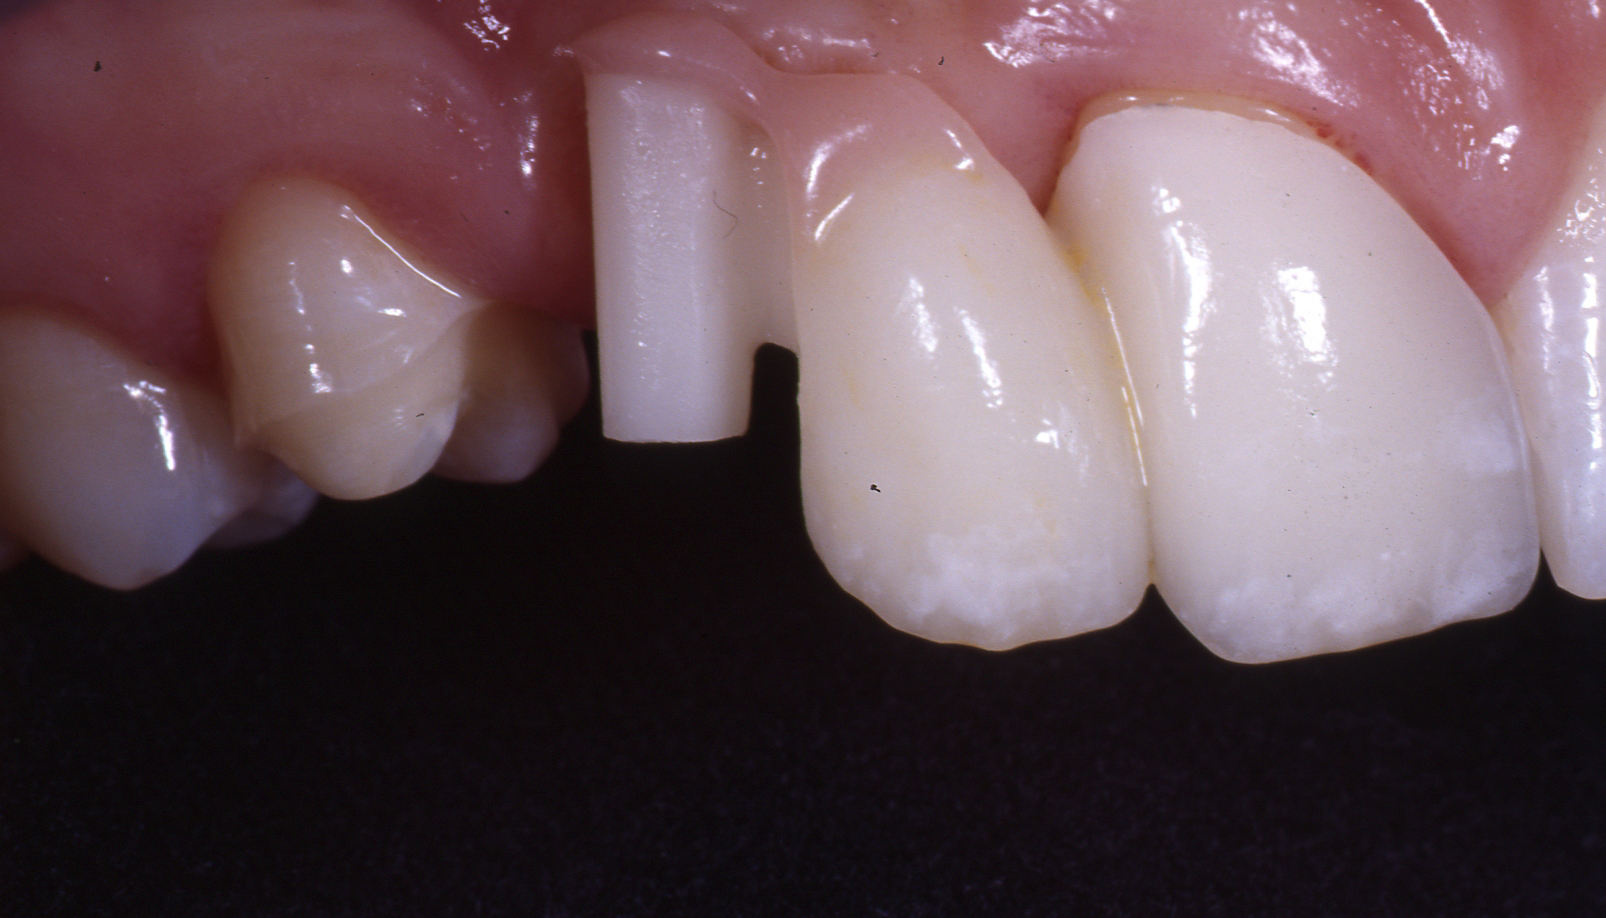

Metallfreie Frontzahnkronen mit individueller keramischer Verblendung.

Kombination aus vollkeramischen Frontzahnkronen und metallbasierten Seitenzahnkronen mit dünn auslaufenden Rändern.

Frontzahnkronen Oberkiefer neu zur Verbesserung der Ästhetik.